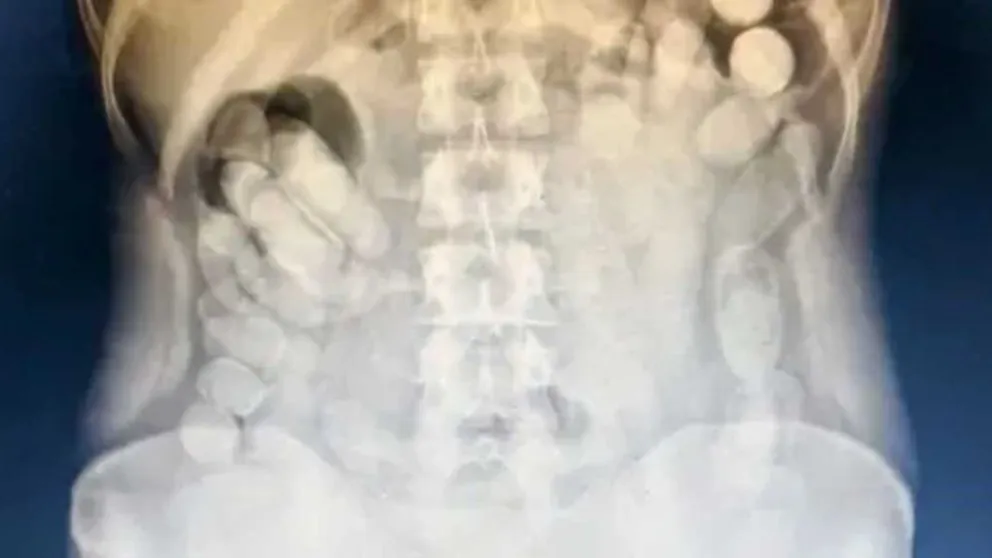

Mujer viajaba con más de 100 cápsulas de cocaína en el estómago: fue detenida en un control vial junio 18, 2025 0 About The Author See author's posts Navegación de entradas Anterior: Arrancó la zafra de liebres en Esquel: cuánto pagan por pieza y qué permisos se necesitanSiguiente: Cami Mayan y su demanda de 6 millones de dólares contra Alexis Mac Allister Deja una respuesta Cancelar la respuestaTu dirección de correo electrónico no será publicada. Los campos obligatorios están marcados con *Comentario * Nombre * Correo electrónico * Web Guarda mi nombre, correo electrónico y web en este navegador para la próxima vez que comente. Δ Noticias Similares Venezuela redujo en un 400 por ciento la inflación interanual aunque acumula más del 50 por ciento en 2026 Redaccion2 marzo 7, 2026 0 Irán anunció que no atacará a países vecinos salvo que lancen ofensivas contra su territorio Redaccion2 marzo 7, 2026 0 La AFA fue clave en el traslado de Nahuel Gallo Redaccion2 marzo 7, 2026 0